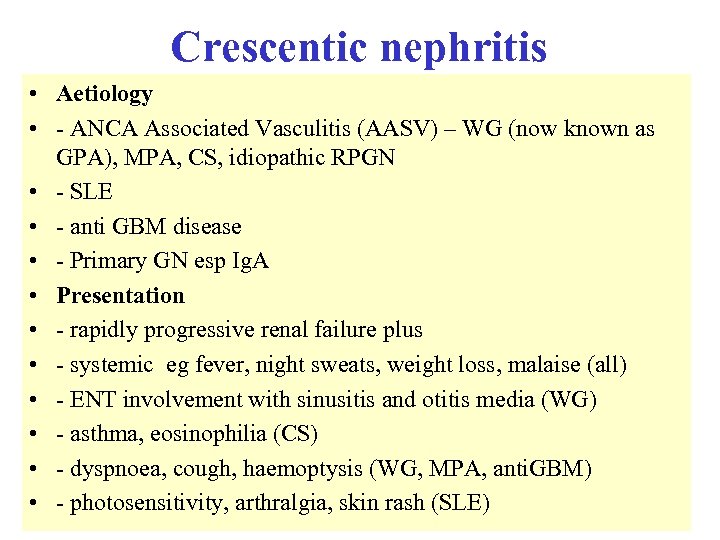

Crescentic nephritis • Aetiology • - ANCA Associated Vasculitis (AASV) – WG (now known as GPA), MPA, CS, idiopathic RPGN • - SLE • - anti GBM disease • - Primary GN esp Ig. A • Presentation • - rapidly progressive renal failure plus • - systemic eg fever, night sweats, weight loss, malaise (all) • - ENT involvement with sinusitis and otitis media (WG) • - asthma, eosinophilia (CS) • - dyspnoea, cough, haemoptysis (WG, MPA, anti. GBM) • - photosensitivity, arthralgia, skin rash (SLE)

Crescentic nephritis • Aetiology • - ANCA Associated Vasculitis (AASV) – WG (now known as GPA), MPA, CS, idiopathic RPGN • - SLE • - anti GBM disease • - Primary GN esp Ig. A • Presentation • - rapidly progressive renal failure plus • - systemic eg fever, night sweats, weight loss, malaise (all) • - ENT involvement with sinusitis and otitis media (WG) • - asthma, eosinophilia (CS) • - dyspnoea, cough, haemoptysis (WG, MPA, anti. GBM) • - photosensitivity, arthralgia, skin rash (SLE)